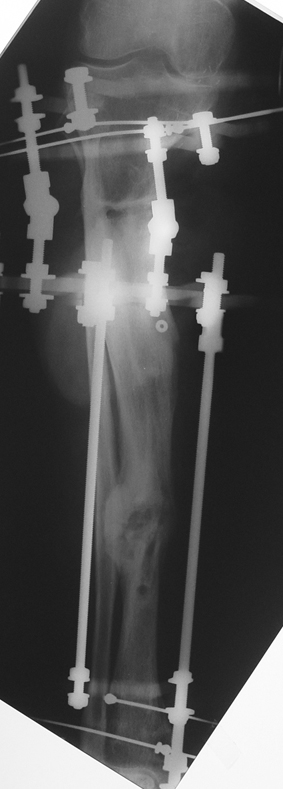

Kaynamayan kemik uçlarının çıkartılması, damarlı fibula veya fibula grefti, damarlı kas greftleri ile birlikte internal fiksasyon uygulamaları, elektrik stimulasyon gibi uygulamalar kaynamamada bir şeçenektir. Fakat kısalık ve deformite gibi ek patolojiler tedavisinde kısıtlı kalmaktadır. İlizarov eksternal fiksatörü ile uygulanan distraksiyon osteogenezi uygulamaları ile birlikte yapılan psödoartroz sahasından akut kısatma ve aynı kemikteki diğer segmentten uzatma yapılmaktadır.

Ilizarov ve arkadasları, kendi geliştirdikleri yöntem ve fiksatörle, aynı anda, hastanın günlük aktivitelerini kısıtlamadan, eklem fonksiyonlarını koruyarak kaynamayı basarmıs,deformiteyi düzeltmis, uzunlugu yeniden sağlamıstır. Bu teknik sayesinde kemik defektlerinin kapatılması ve enfeksiyon gibi hastaya morbidite getiren ek patolojiler giderilmiş aynı zamanda kısalıkta telafi edilmiştir.

Vaka 2